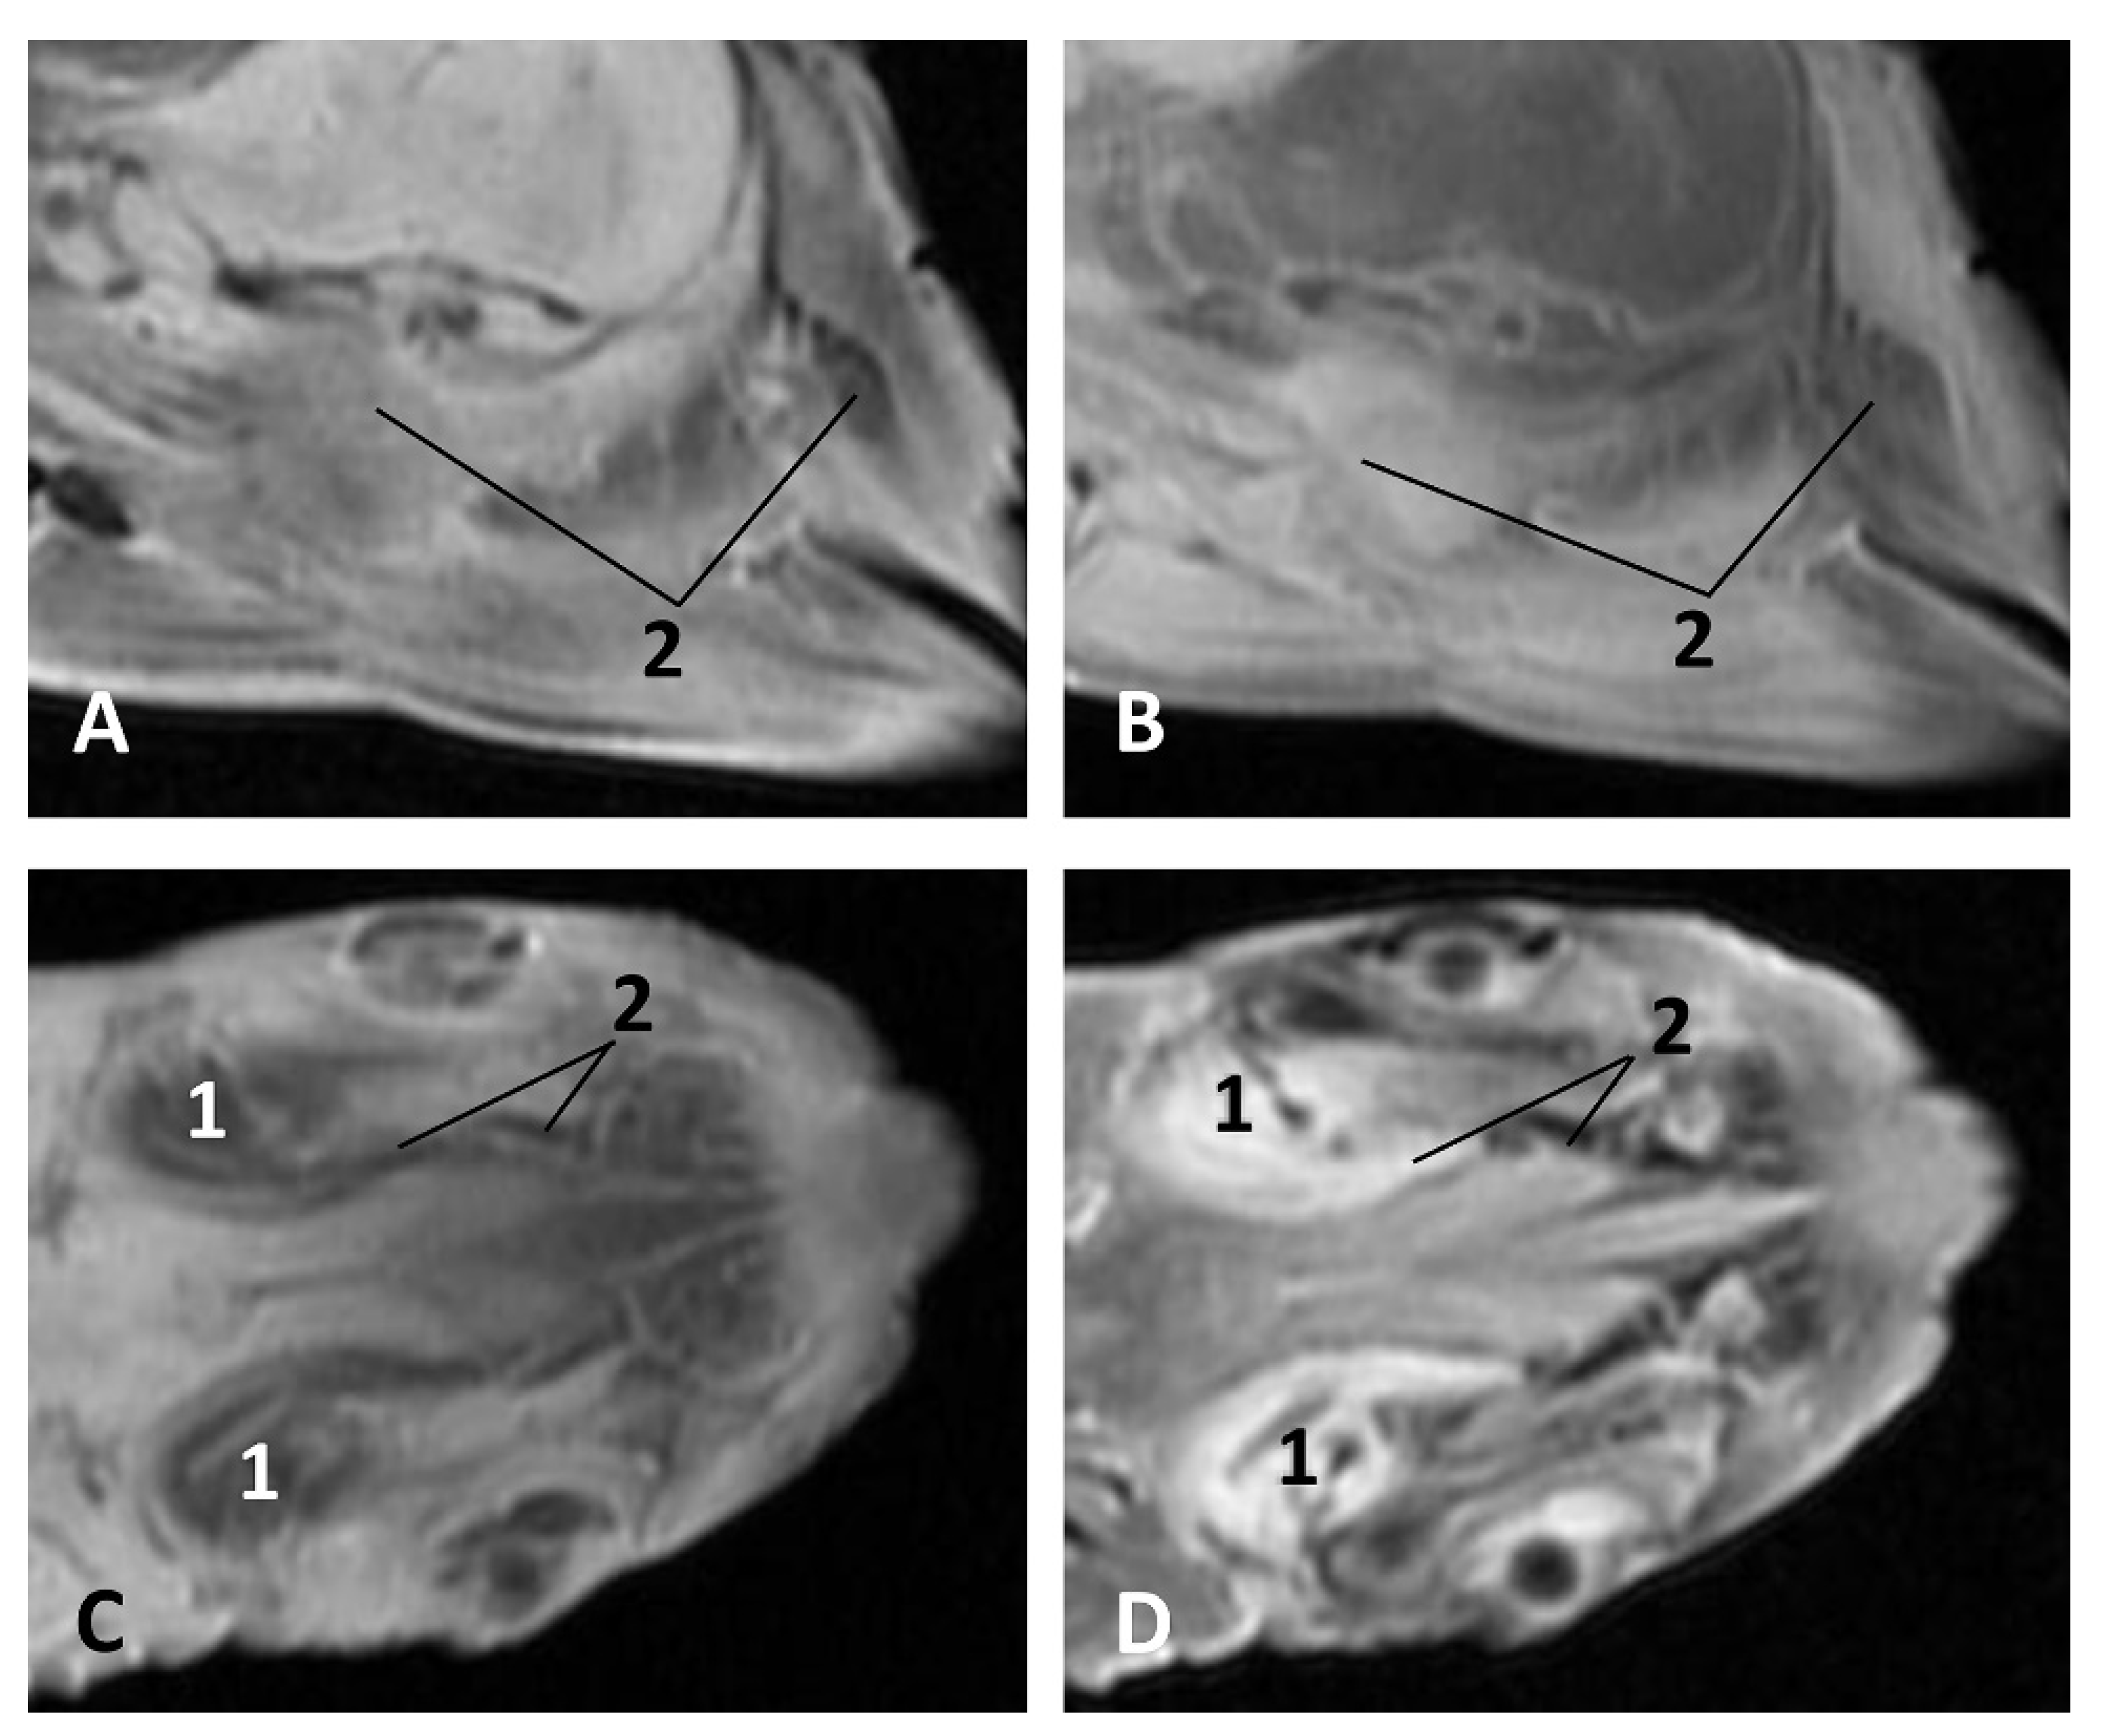

- Sectional anatomy

The three coronal sections, in a newborn Stenella coeruleoalba (scomu2), extend from the floor (Figure 34A) to the roof of the oral and pharyngeal cavities (Figure 34B,C). In these images it was possible to observe the proximity to the mandible channel tissue and the pharyngeal orifices of the auditory tubes crossing the pharyngeal muscles. It is easy to medially differentiate the air area (near the auditory tube and nasopharynx and laterally to the cribriform area) (Figure 34).

Figure 34.

(A–C) Coronal sections of head at level of eyes, ear, pharyngeal and oral cavity. These three sections show the extension and connection between the pterygopalatine recess (pterygoid sinus) and the PDAT and between the nasopharynx and PDAT. (A,B) Dorsal view (C) Ventral view. scomu2. 1, Middle and inner ear; 2, Pharyngeal orifices of the auditory tube; 3, Pharyngeal diverticulum of the auditory tube: air area; 4, Pharyngeal diverticulum of the auditory tube: vascular area; 5, Vomer and choanas; 6, Pharyngeal muscles; 7, Piriform recess; 8, Laryngeal cartilages: aditus laryngis; 9, Hard palate (maxillary bones); 10, Tongue (sectioned) 11, Mandibles; 12, Labial vestibule; 13, Oral cavity.

The two sagittal sections in a juvenile Stenella coeruleoalba (scomu3) were made para-sagittally at the level of the ear. It shows that this area (PDAT) extends rostrally to the inner and middle ear crossing below the basal bones of the cranium to arrive to the pterygopalatine recess (pterygoid sinus) and finish dorsally at the maxillopalatine fossa (Figure 35).

Figure 35.

(A,B) Detailed serial sagittal sections at level of the pharyngeal diverticulum of the auditory tube with an anfractuous mucosa filled with a heterogeneous content. It extends up to the maxillopalatine fossa rostral to the eyeball. scomu3. 1, Middle and inner ear; 2, Pharyngeal diverticulum of the auditory tube; 3, Occipital bone: basilar part; 4, Basisphenoid bone; 5, Presphenoid and ethmoid bones; 6, Pterygoid bone; 7, Palatine bone; 8, Maxilopalatine fossa (pterygopalatine fossa in domestic mammals); 9, Pterygopalatine recess (pterygoid sinus).